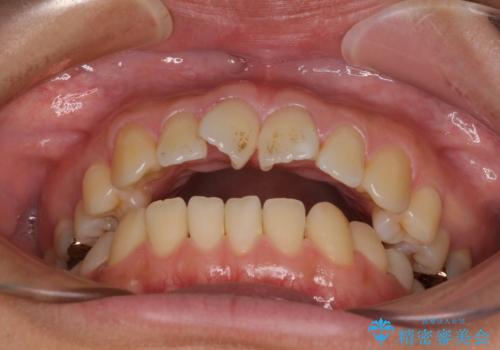

- 下顎小臼歯が欠損しており、さらに上顎が全体的に突出していることを気にして来院された患者様です。

下顎は片方の小臼歯が欠損していたため、正中がずれた上に、上下前歯が接触していない状態でした。

上顎左右の小臼歯2本および下顎小臼歯を1本抜歯し、補助装置を用いて上顎大臼歯が前方に移動しないように固定した上で、ワイヤー装置にて矯正治療を行うこととしました。